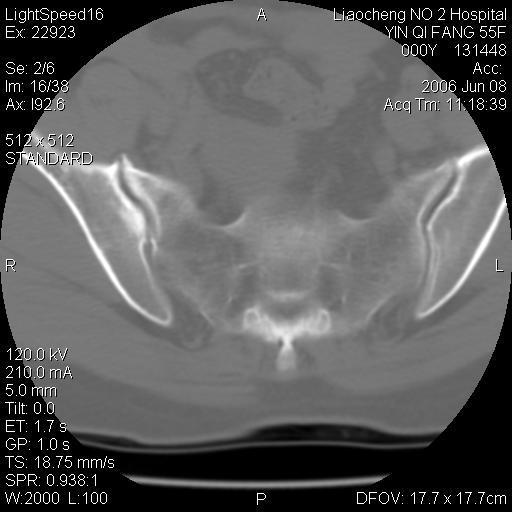

女,55岁,十余年前骶尾骨摔伤,x线平片诊断骶骨裂纹骨折,现在骶尾部又疼痛2月,x线怀疑骶骨左下部骨质破坏。大家看看,是不是先天变异。正常人不是只有4个骶孔吗?怎么此病例有5个?

两侧骶髂关节炎,确实做得很漂亮

众口一词啊,图象确实漂亮,羡煞人也!右侧骶髂关节间隙变窄,相对缘增生硬化,髂骨侧增生明显。左侧轻微类似改变,考虑双侧骶髂关节炎。余未见异常。

考虑双侧骶髂关节炎。余未见异常。

支持骶髂关节炎,3d做得很漂亮!!!!

图象很漂亮,骶骨未见异常,感觉右侧骶髂关节髂骨面密度增高,不知是否异常?

五个孔也是正常的呀;